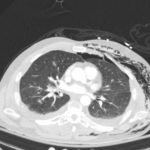

Plain film anteroposterior (AP) radiography of the chest shows left-sided subcutaneous emphysema (red arrow) with overlapping muscle striations of the pectoralis major (green arrow). After chest tube placement (blue arrow), AP chest radiography shows persistent left-sided subcutaneous emphysema (red arrow). CT of the chest shows pneumomediastinum (blue arrow), left apical pneumothorax (pink arrow), and subcutaneous emphysema (red arrow) at the level of T2. At the level of T6, rib fractures can be visualized on the CT (yellow arrow). At the level of T8, left sided pneumothorax is also seen (pink arrow) as the absence of lung tissue on CT.

Injuries of the thorax account for 25% of all mortality in trauma patients, of which many are preventable deaths by simple interventions.1,2 One sign commonly seen in patients with chest trauma is subcutaneous emphysema. The presence of this underlying emphysema has been suggested to be a sign of injury to the respiratory tract, making it clinically significant.3,4 Specifically, subcutaneous emphysema has been shown to be a clinical predictor of occult pneumothorax, with an odds ratio of 5.47.3 Furthermore, these injuries to the respiratory tract (pneumothorax /hemothorax, pneumomediastinum, etc.) can lead to hemodynamic instability and respiratory failure.4-6

In this patient, given the findings of multiple bilateral rib fractures, bilateral hemothorax/pneumothorax and multiple spine fractures, bilateral chest tubes were placed which had immediate output. The patient was admitted to surgical intensive care unit for chest tube management, pulmonary hygiene and further management of his other injuries.